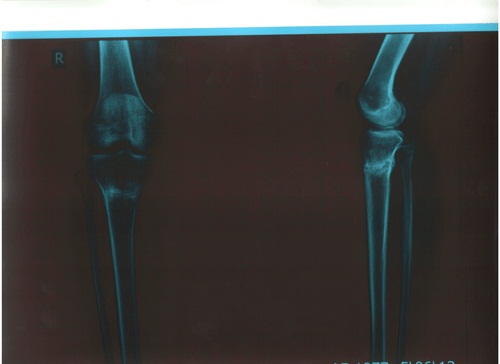

Рентгеновские снимки в 2 месяца после снятия аппаратов!

Вложения

рент.jpg

р-л.jpg